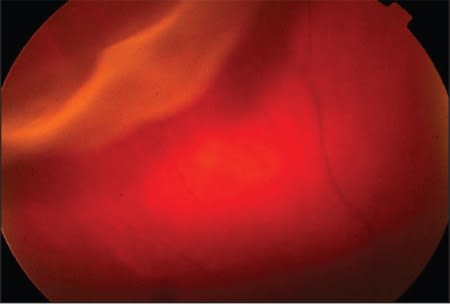

Then Dr. Apte transitioned back to discussing RD. He presented a mouse model of RD (Figure 5), in which a partial RDs had been created with viscoelastic. The mouse retina tended to reattach by day 3, with complete reattachment by day 7. By presenting laser-capture microdissections of the mouse retina, Dr. Apte was able to demonstrate how macrophages and microglial cells appeared in greater quantities in the detached retina. When cell death occurred, it was the macrophages and not the microglial cells that played the key role (Figure 6).

Figure 5. A mouse model of retinal detachment.